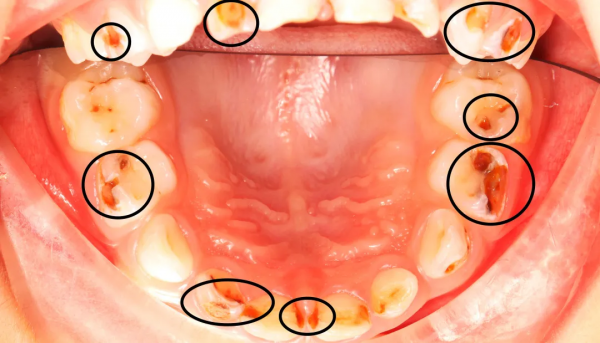

△密密麻麻的小黑牙和洞洞△

童童乳牙蛀了17顆,任其發展下去,勢必影響恆牙的萌出,還可能導致營養不良。